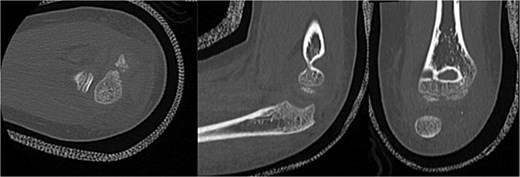

Initial radiographs following closed reduction and casting demonstrated fractures of the proximal ulna and radial neck, with improved alignment but limited bony detail (Fig. 1a and b). Elbow effusion was also noted. A CT scan performed 3 days later showed 18° apex-medial angulation of the radial neck fracture, slight inferior subluxation of the radial head, and linear calcification near the ulnotrochlear interval, concerning for an intra-articular fragment (Fig. 2).

(a, b) Initial radiographs after closed reduction, showing proximal ulna and radial neck fractures.